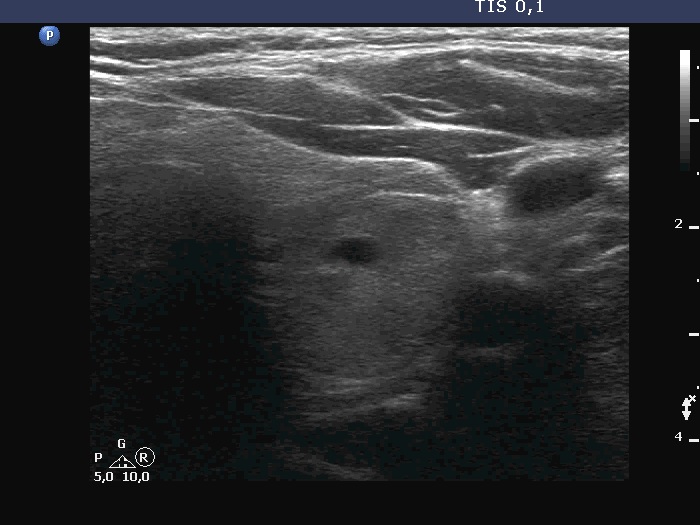

Examination a year after the first visit (third row of images):

Clinical presentation: The patient had no complaints.

Palpation: no abnormality.

Laboratory tests: TSH 1.60 mIU/L, FT4 15.6 pM/L, aTPO 12 U/mL.

Ultrasonography: The dorsal part of the right lobe remained hypoechoic. The nodule in the left lobe has increased in size and presented halo and signs of perinodular vascularity.

Cytology of the nodule resulted in benign lesion.

Suggestion: repeat examination in three years.

Comment. In the active phase of subacute thyroiditis, a nodule can be obscured. The real structure of the thyroid can be revealed only when the hypoechogenicity disappears or decreases significantly.